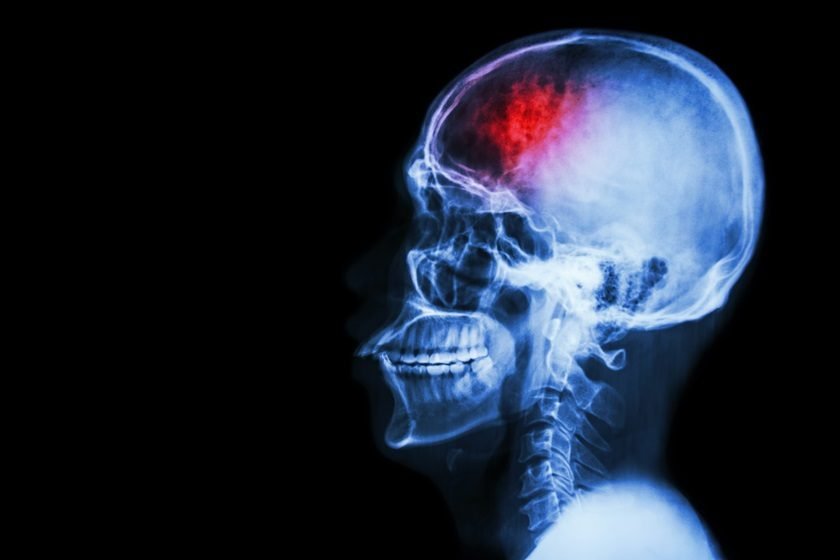

Segundo a Organização Mundial de AVC (WSO), uma em cada seis pessoas terá um derrame ao longo da vida – o mesmo estudo garante, também, que 90% dos casos podem ser evitados com boa alimentação e prática de exercícios físicos. Cerca de 25% dos indivíduos que sofrem um acidente vascular cerebral acabam morrendo, e mais da maioria dos sobreviventes fica com sequelas graves.

O tempo é essencial para quem sofre um AVC (o atendimento demorado, que leve mais de 4h30min para ocorrer, pode dificultar o tratamento) e a tecnologia vem se revolucionando para auxiliar melhor o paciente. Usando como base quatro biomarcadores, o software criado pela startup holandesa Nico.lab acelera o diagnóstico e assistência a derrames.

Baseado em inteligência artificial, o StrokeViewer analisa resultados de exames e, em poucos minutos, dá um diagnóstico e sugere o tratamento. O algoritmo também aprende com sua própria história e ajuda os médicos com informações extras sobre o funcionamento do cérebro.

O StrokeViewer já foi testado em 3 mil pacientes na Holanda e conseguiu aprovação de 15 hospitais no país para ser usado no diagnóstico de AVC. Por causa de todo sucesso, o software recebeu um prêmio europeu de 500 mil euros, além de 3 milhões de euros de um grupo de investidores australianos para um IPO (oferta pública inicial) lá. O programa da Nico.lab deve participar ainda de estudos clínicos na Austrália e na América do Norte. Não há previsão de quando a tecnologia chegará ao Brasil.